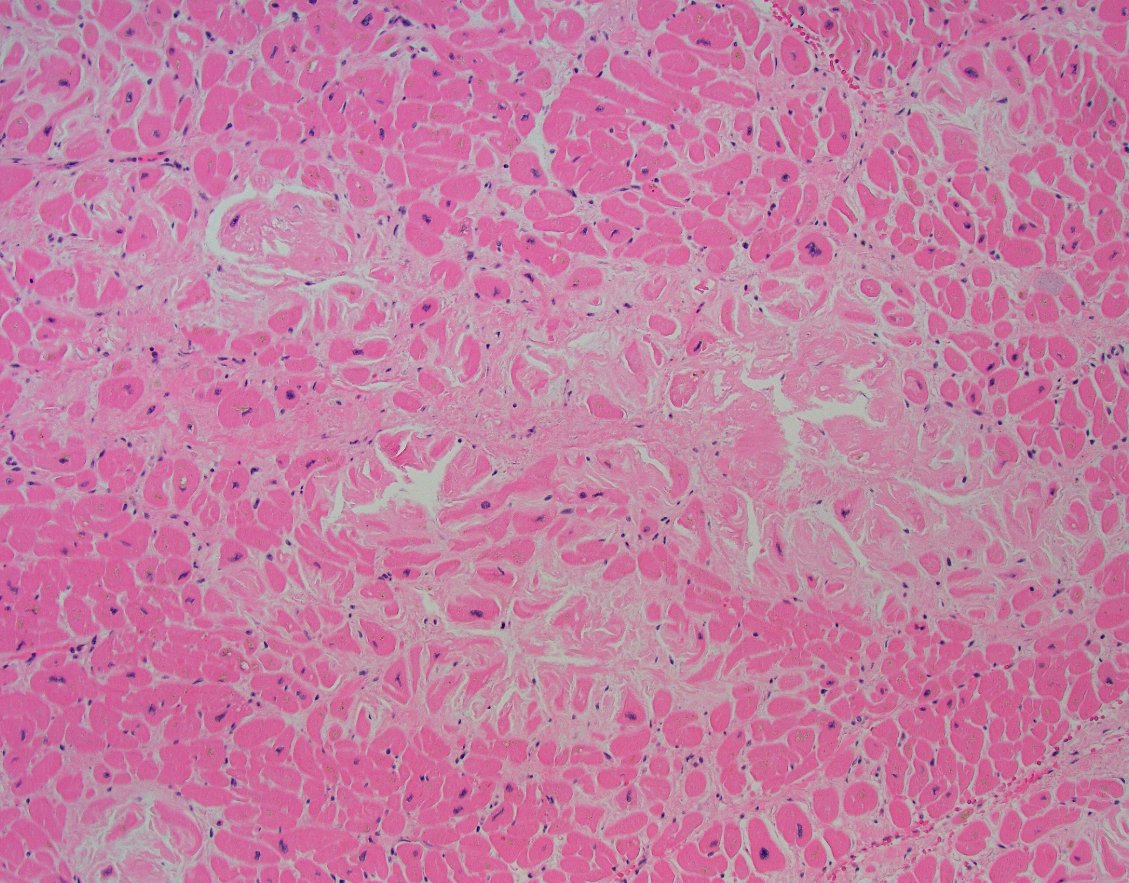

Autopsy surprise. Presumed RA assc. interstitial lung dx. #autopsypath revealed talcosis as underlying cause of ILD. Abundant polarizable crystals +giant cell rxn diffusely in fibrotic septea. Also focal similar findings in myocardial tissue. Remote hx of IVDU. #foresnsicpath